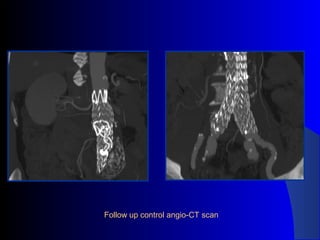

The document discusses the clinical application of the Endurant stent graft system in treating aorto-bisiliac aneurysms, detailing procedures performed on two male patients aged 72 and 73. Each patient had a history of dyslipidemia and carotid atherosclerosis, with procedures involving the bilateral bell bottom technique and the use of coils and fibrin glue. It includes pre-surgery imaging, intrasurgery angiography, and follow-up control scans to monitor outcomes.